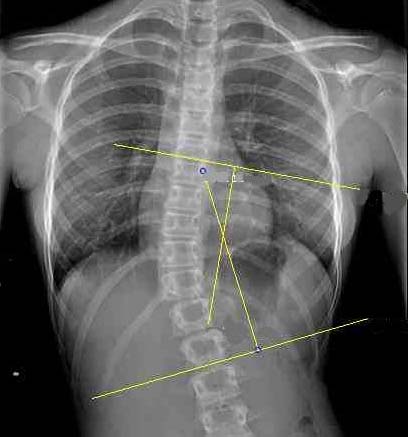

LA ROTAZIONE VERTEBRALE

La torsione delle colonna sul proprio asse è uno degli elementi caratteristici della scoliosi vera. Il termine rotazione vertebrale esprime il grado di torsione della vertebra apicale di una curva, generalmente la vertebra più ruotata.

Sono stati descritti diversi metodi per esprimere la rotazione vertebrale, i più comuni fanno riferimento alla posizione dei peduncoli, più o meno asimmetrici, ricordiamo in particolare il metodo di Nash & Moe, il metodo di Perdriolle e il metodo di Raimondi.